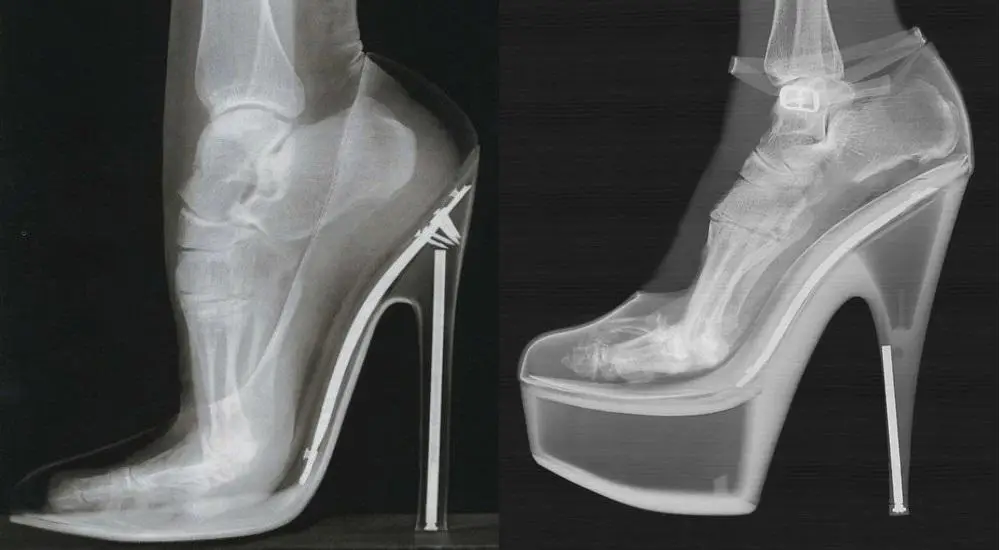

Consideration should be given to the feet’s position when wearing heels that are higher than 10 cm. Platforms are most recommended. Please see the link leading to the x-ray below. Both shoes have approx. 14cm heels. The left shoe has no platform, the right shoe has a 4cm high platform. The instep of the woman wearing the heels without platforms is almost vertical, very unnatural, while the instep of the woman wearing platforms is much closer to a natural angle (which is about 21 degrees), even though the heels themselves are the same height. Also, the arch of the foot wearing non-platform heels is more unnaturally curved, but the arch of the foot wearing platform heels is not so unnaturally curved. This means that the woman’s entire weight is on the balls of her feet when wearing non-platform heels, but the weight of the woman wearing platform heels is distributed more evenly between the balls and heels of their feet; Even though she’s wearing 14 cm heels, it feels more like she’s wearing 10 cm heels! For all day wear, it is best to wear heels 10cm or less, and save the stilettos without platforms 10cm and highter for limited wear and special occasions.